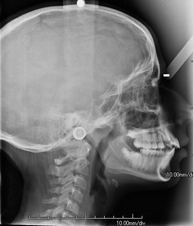

- RX Cráneo

Técnica mediante la cual, utilizando rayos X, se obtienen imágenes del cráneo para su estudio. Indicaciones: traumatismo, cierre precoz de suturas craneales. - RX Senos Paranasales

Técnica mediante la cual, utilizando rayos X, se obtienen imágenes del cavum para su estudio. Indicaciones: dificultad respiratoria, anginas de repetición en lactantes y niños. - RX Columna cervical

Técnica mediante la cual, utilizando rayos X, se obtienen imágenes de la columna cervical para su estudio. Indicaciones: traumatismo, contractura cervical, dolor articular. - RX Huesos propios nasales

Técnica mediante la cual, utilizando rayos X, se obtienen imágenes del cuello para su estudio. Indicaciones: estudio de bultos o nódulos. - RX Charnela

Técnica mediante la cual, utilizando rayos X, se obtienen imágenes de la charnela o de la base del cráneo para su estudio. Indicaciones: estudio de malformaciones congénitas.

- Cervical spine X-ray

This technique uses X-ray rendered imaging for examining the cervical spine. Indicated for: trauma, cervical pain.